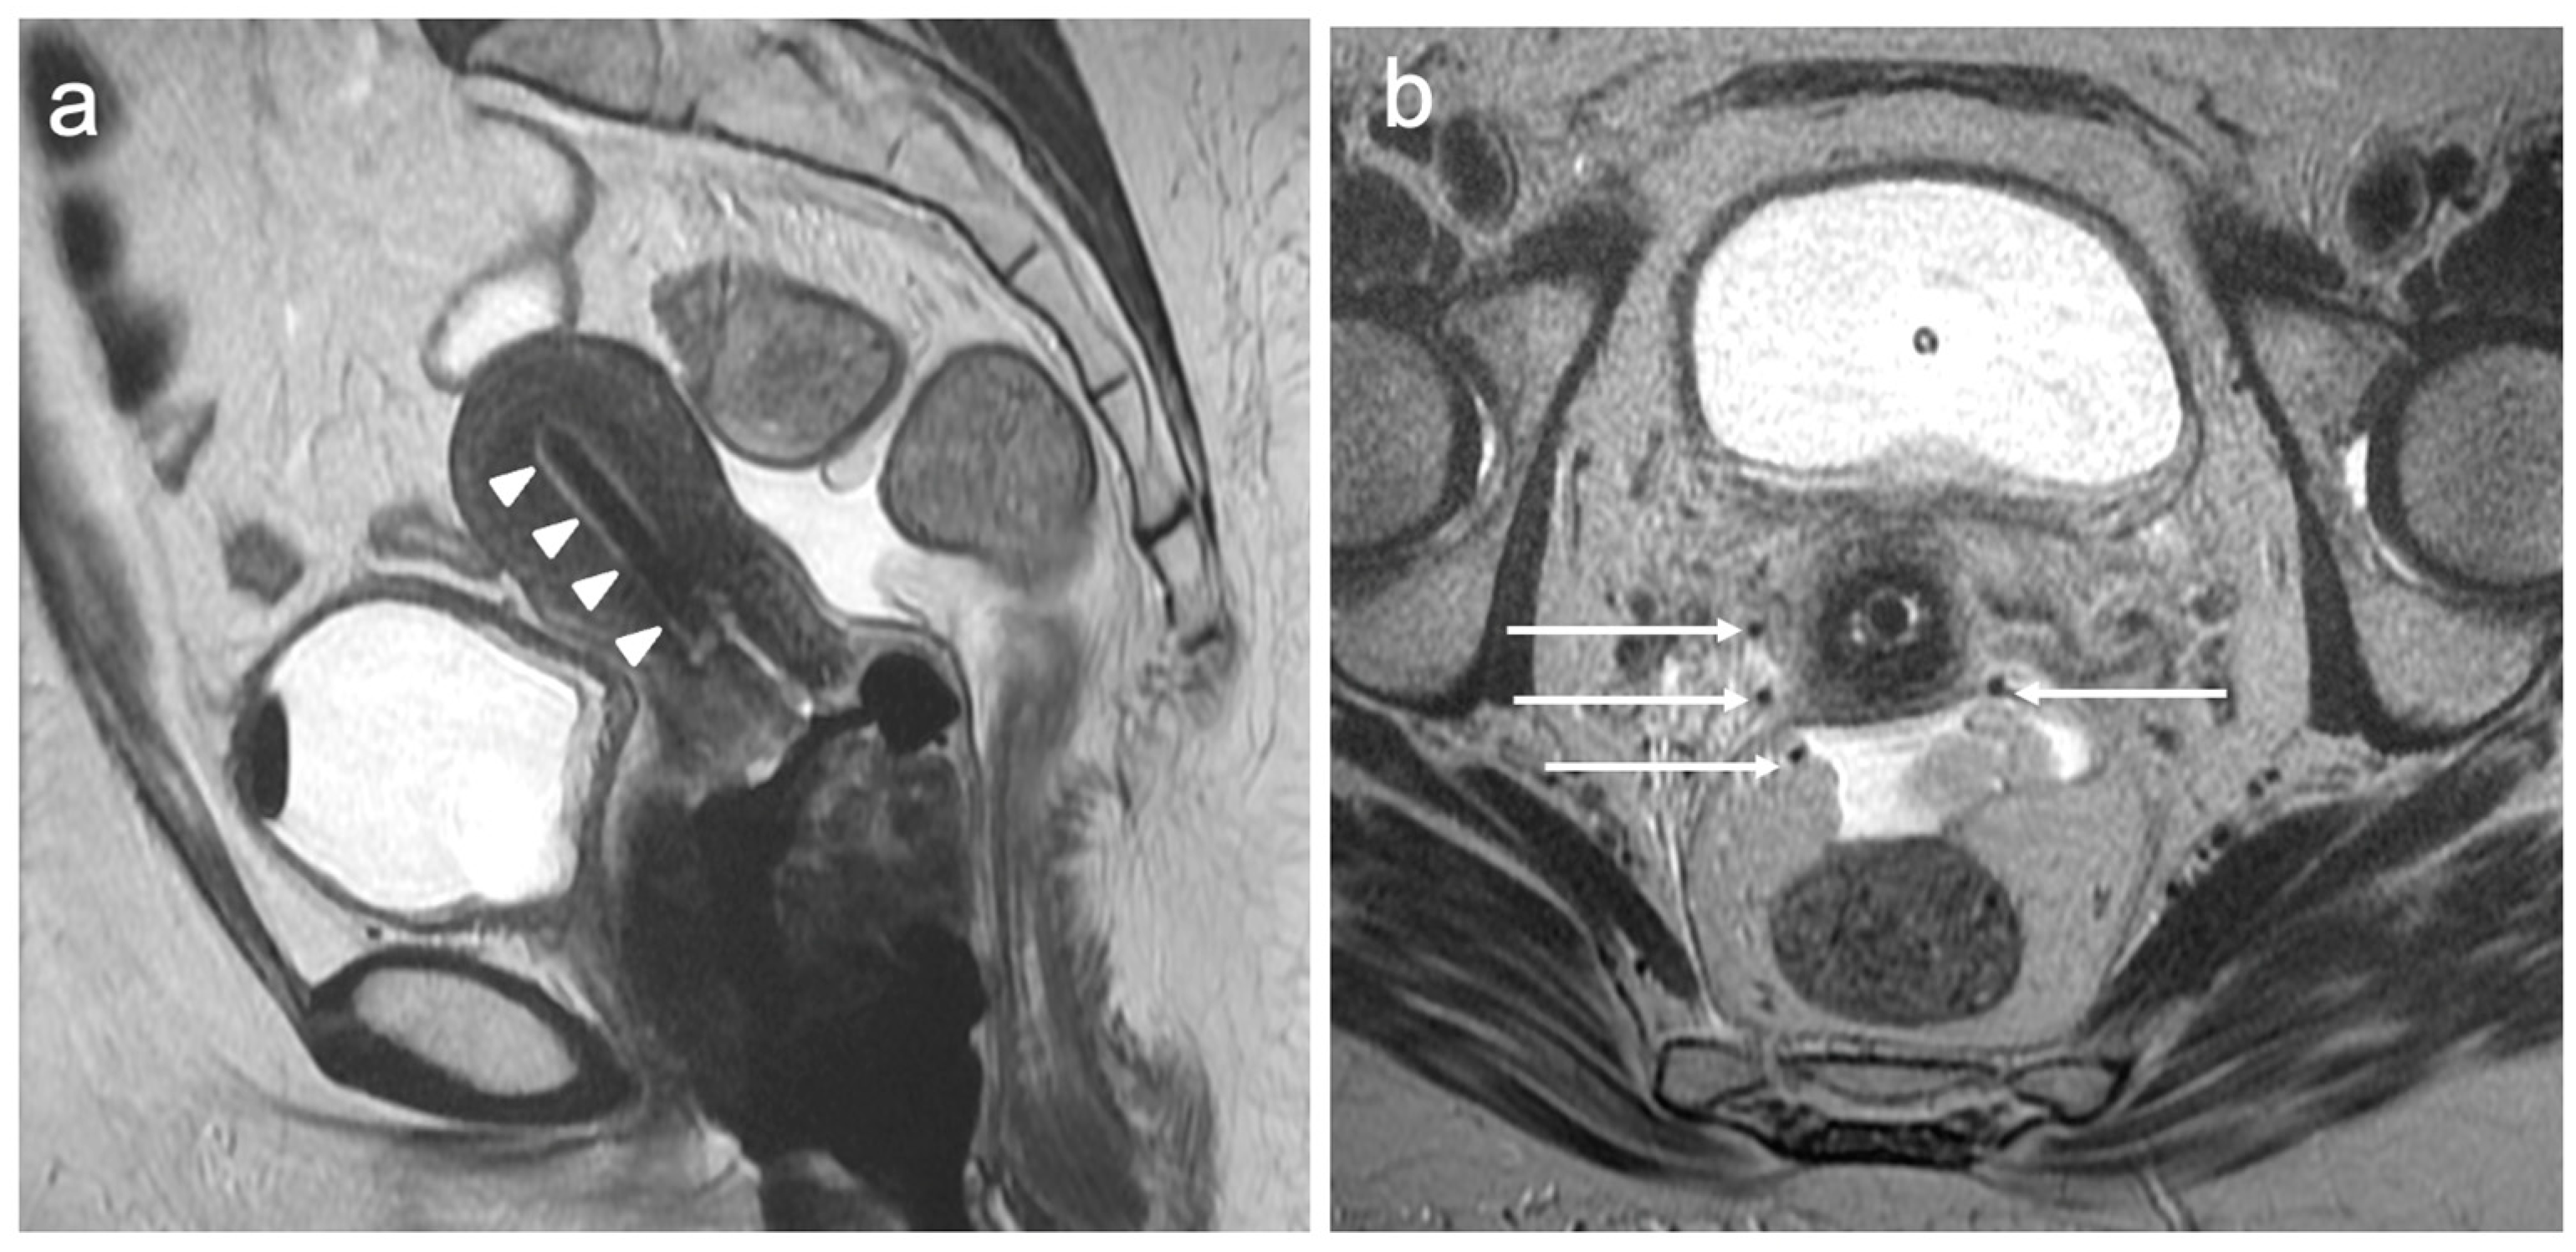

6. FIGO Stage III

7. FIGO Stage IV

| Stage III | Involves the lower third of the vagina and/or extends to the pelvic wall and/or causes hydronephrosis or non-functioning kidney and/or involves pelvic and/or paraaortic lymph nodes |

| IIIA | Involves lower third of the vagina, with no extension to the pelvic wall |

| IIIB | Extension to the pelvic wall and/or hydronephrosis or non-functioning kidney (unless known to be due to another cause) |

| IIIC | Involvement of pelvic and/or paraaortic lymph nodes |

| IIIC1 | Pelvic lymph node metastasis only |

| IIIC2 | Paraaortic lymph node metastasis |

| Stage IV | Spread to adjacent and distant organs |

| IVA | Rectal or bladder involvement |